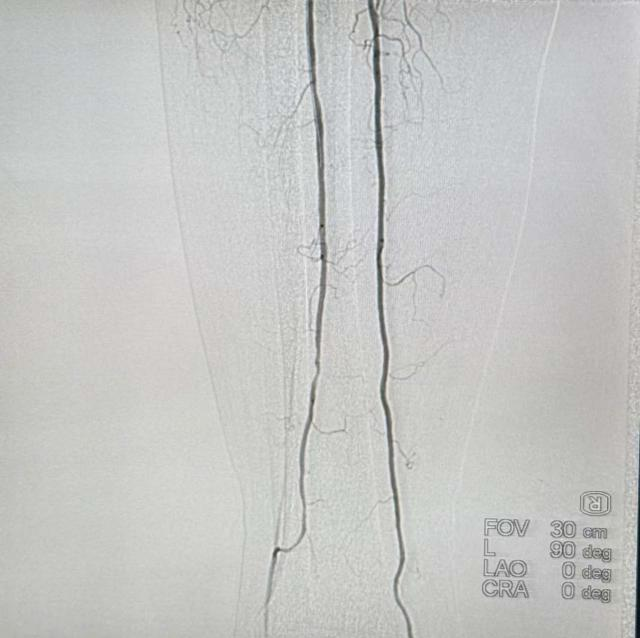

在血栓负荷基本清除后,团队进一步行球囊扩张及支架植入术处理狭窄的血管基础病变。术后即刻造影显示,股浅动脉及腘动脉血流通畅,远端胫后动脉及腓动脉显影良好。

术后血流通畅